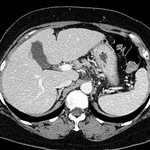

[画像診断]肝臓の所属リンパ節腫大、良悪性について(HCCリンパ節転移、慢性肝炎など)【最終警告】 2011-03-30